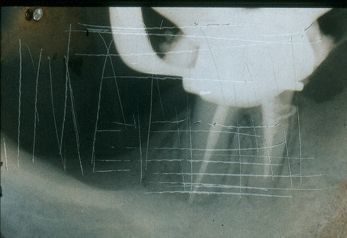

Radiogafía a revés Las lineas entrecortadas que se aprecian a la izquierda muestran que la laminilla de plomo se coloco hacia el área vestibular y no palatal.